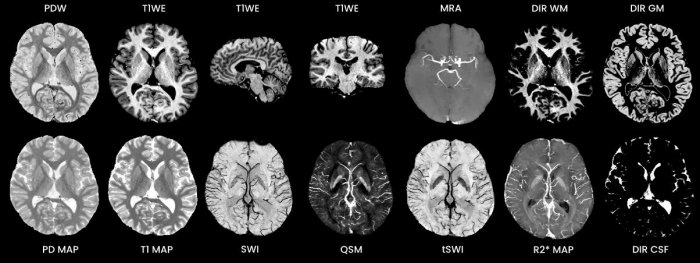

Discover STAGE - Model T1, T2, SWI -Rapid, Quantitative, Comprehensive Brain Imaging

Reduce time for MRI brain protocols by ~30% while improving image clarity.

- 5-minute acquisition at 3T.

- Fully sampled, 3D data.